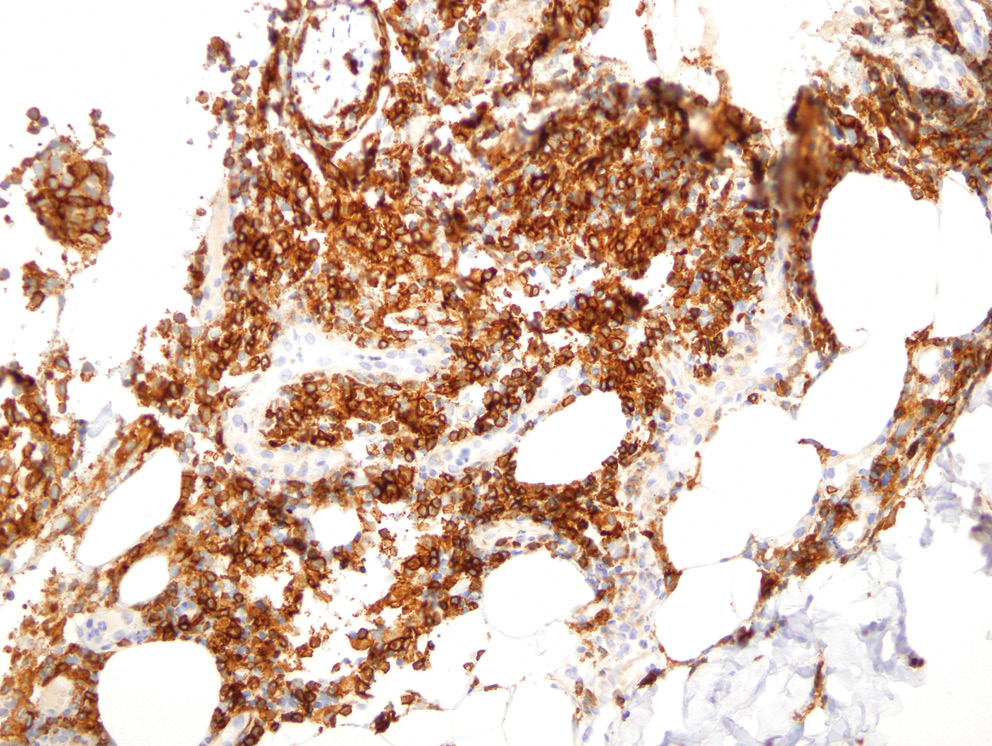

Учитывая отсутствие в биоптате признаков васкулита, гистологический материал пациента был направлен на пересмотр в НИИ онкологии им. Н.Н. Петрова, где было выполнено иммуногистохимическое исследование с антителами ALK, DSF3, CD3, CD4, CD8, CD20, CD30, CD56, Ki-67. По результатам исследования в дерме определялись плотные крупноочаговые инфильтраты, расположенные преимущественно в средних и глубоких отделах дермы и проникающие в дольки подкожной жировой клетчатки (рис. 3). Инфильтраты состояли из крупных лимфоидных клеток с иммунобласто- и центробластоподобной морфологией (рис. 4) и малых лимфоцитов. Крупные лимфоидные клетки экспрессировали CD3+, CD4+ и CD30+, были негативны к ALK (рис. 5–7). Ki-67 (индекс пролиферативной активности) был положителен преимущественно в крупных лимфоидных клетках и составлял примерно 30% всех клеток инфильтрата (рис. 8). Гистологические изменения и иммунофенотип опухолевых клеток соответствовали ЛиП типу С.

Рис. 6. Микрофотография, ×40, иммуногистохимическое исследование с использованием антител к CD4. Определяется выраженная положительная экспрессия CD4 крупными лимфоидыми клетками инфильтрата

Fig. 6. Microphotography, ×40, immunohistochemical assay with anti-CD4 antibodies. There is determined the pronounced expression of CD4 by large ymphoid cells